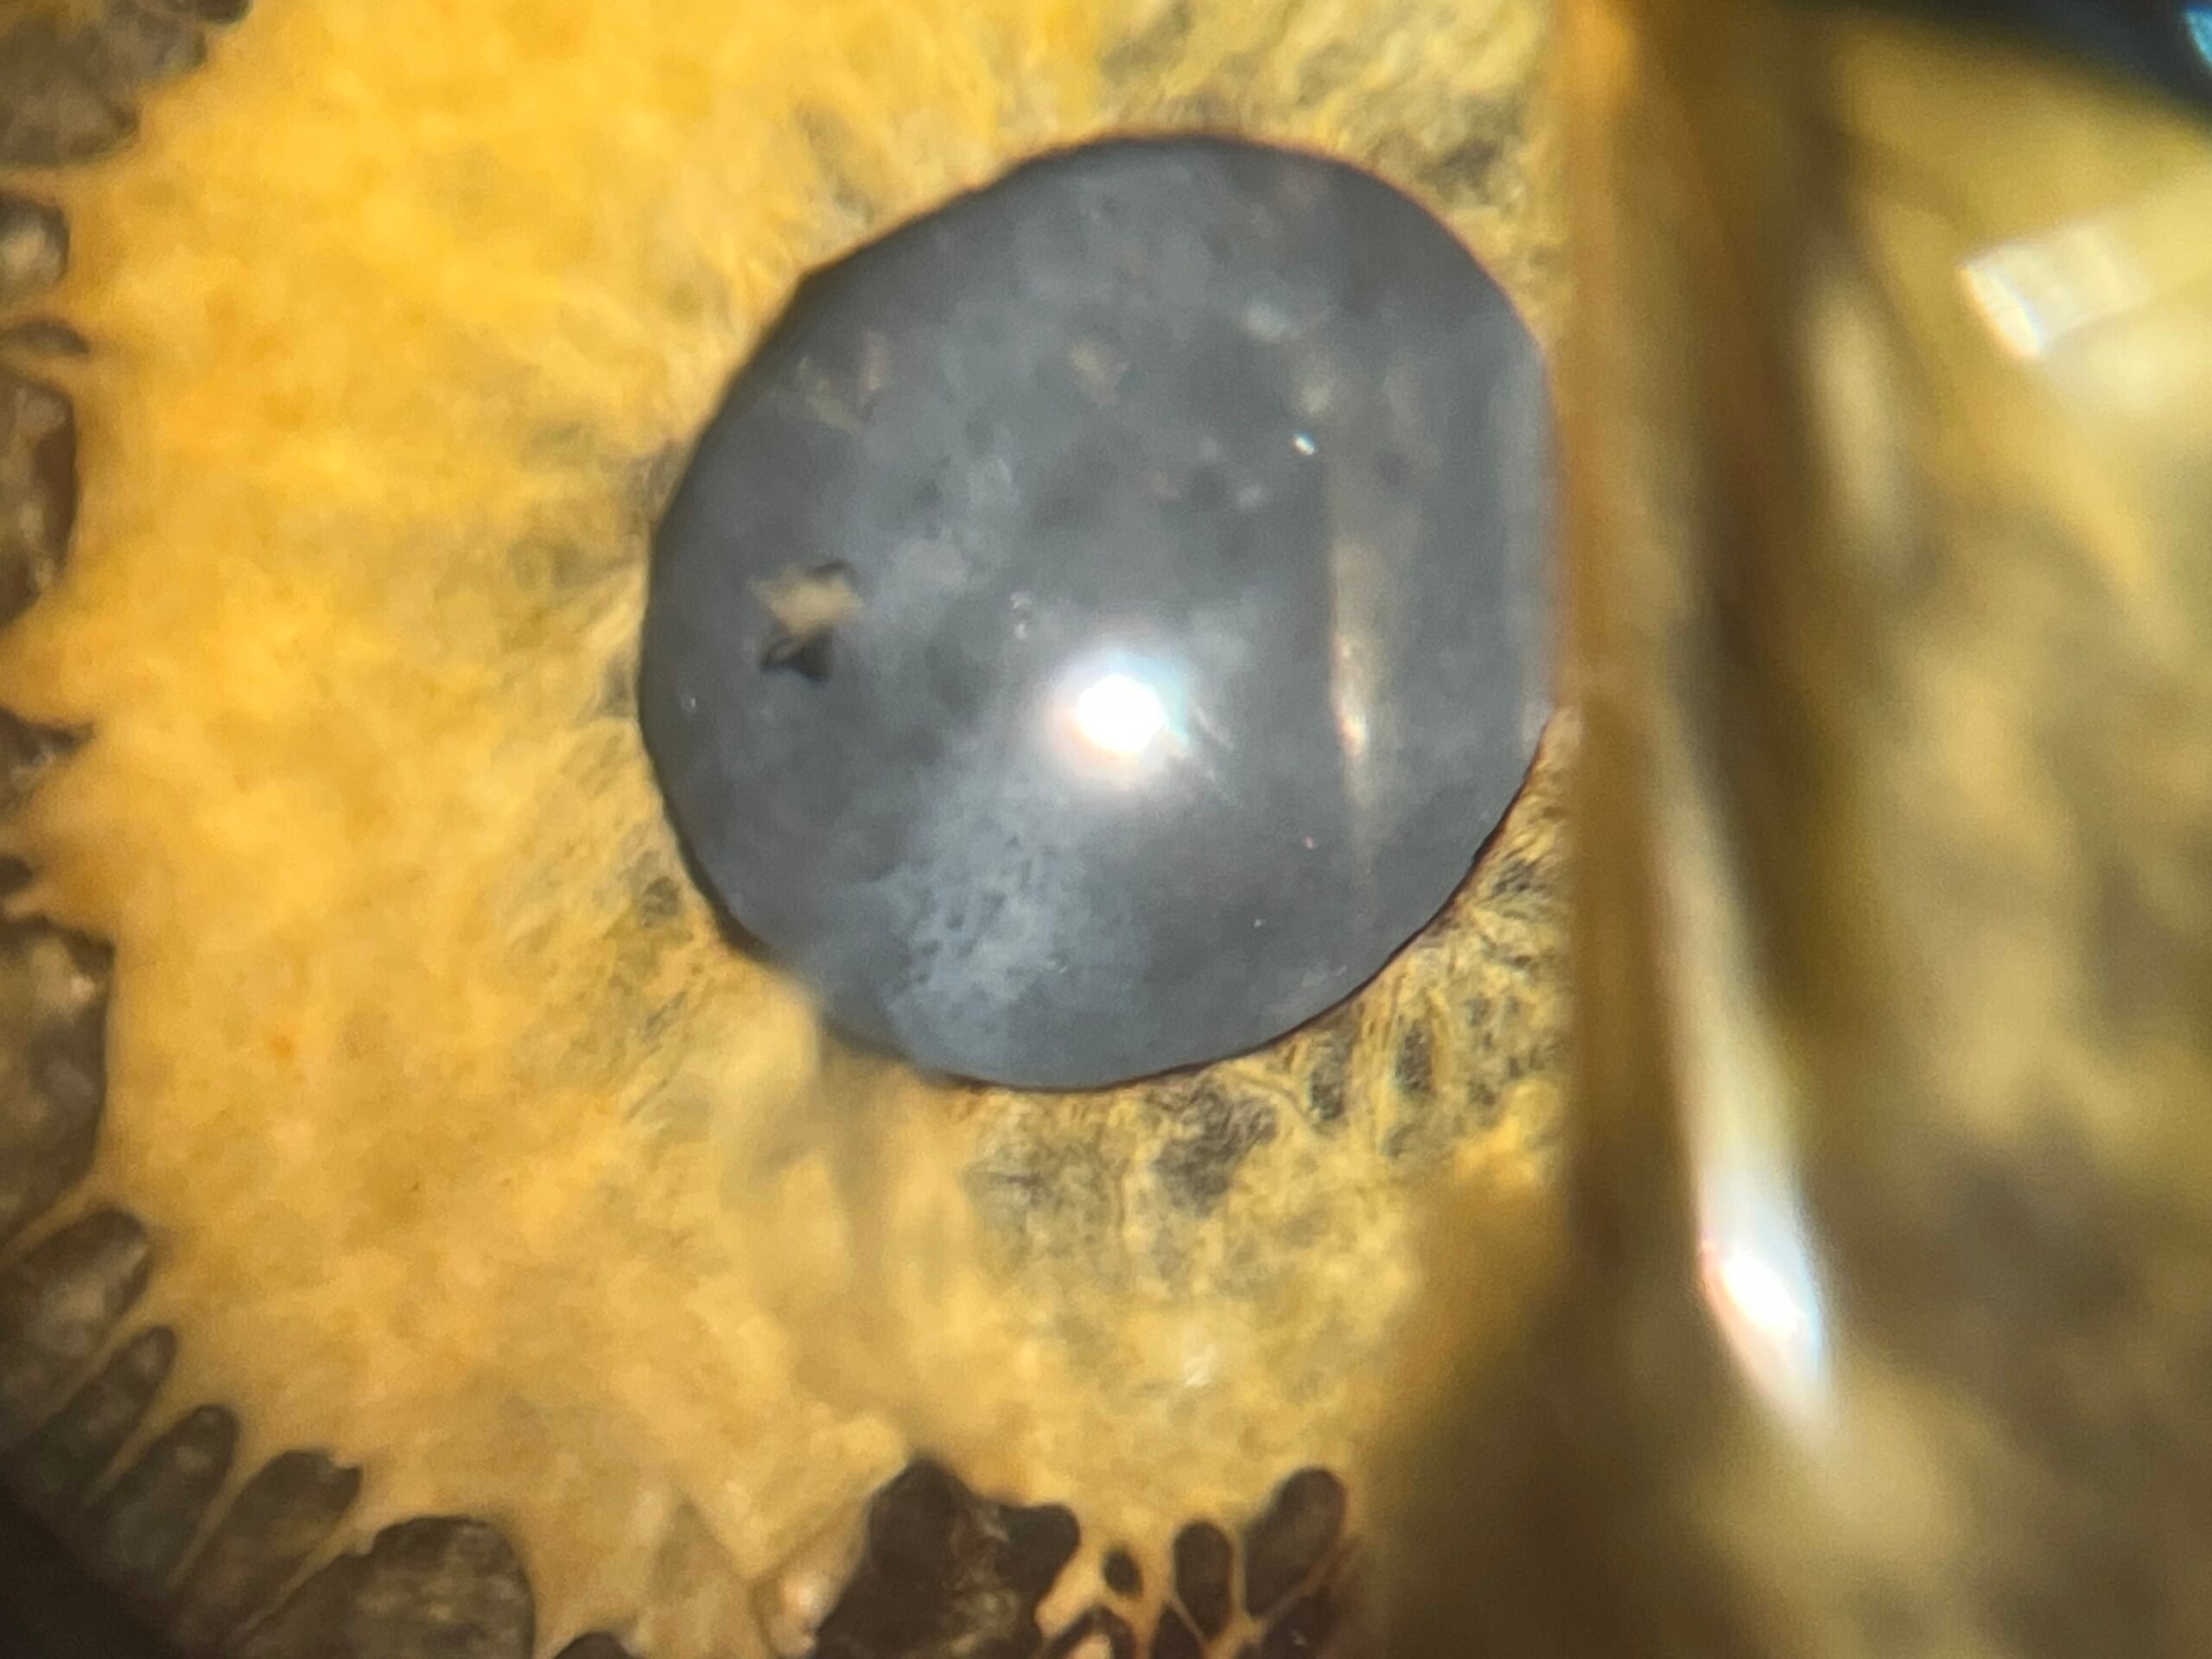

Al respecto, Felipe Graciano Echeverry, médico veterinario especialista en oftalmología y cirugía veterinaria explicó el procedimiento “realizamos la primera cirugía de cataratas de un águila en Colombia y la primera cirugía de cataratas en el mundo de esta especie. Acabamos de operar a Kassandra, un águila real de montaña de 45 años, la cual había perdido completamente su visión; por medio de una cirugía de facoemulsificación logramos a través de un microscopio quirúrgico, ingresar al globo ocular y retirar sus cataratas y con esto esperamos que en los próximos días empiece a recuperar su visión”.